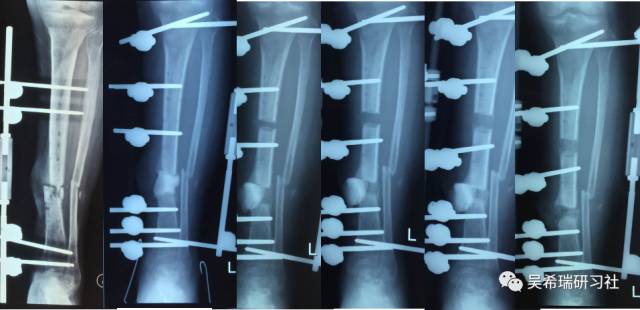

多发骨折车祸伤手术后继发感染,大段骨缺损

去除死骨——骨水泥——植皮

骨搬移

4个月

9个月

剥削植骨

TIPS:开放植骨+针式牵引骨搬移骨水泥Spacer/骨水泥链珠技术剥削植骨技术皮肤牵张技术胫跖骨牵引技术尽早下地走路刺激骨生长,改善骨质量历时2年